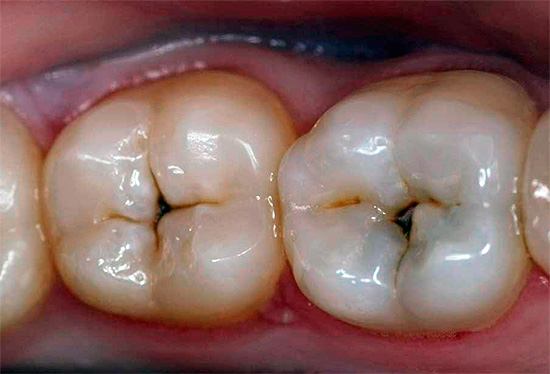

La foto sotto mostra un dente in cui la carie profonda ha portato allo sviluppo della pulpite:

La causa più comune (eziologia) della pulpite è carie profonde. Nel processo di approfondimento della cavità cariata, si verifica la penetrazione diretta o indiretta dei microbi nel tessuto pulpare. Con accesso diretto, l'infezione va direttamente alla polpa aperta e con accesso indiretto, attraverso i tubuli dentinali che penetrano nello spessore della dentina.